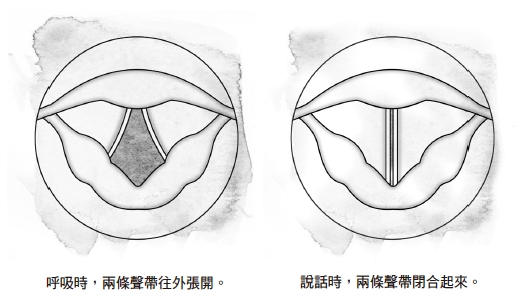

喉头(或者称为「音箱」)位于气管的上方,也就是喉结的位置。喉头里面有两条声带,这两条声带会彼此协调运作。说话时,我们吐出去的空气会经过喉头,从两条闭合的声带中间穿梭而过,往上流动。

1 舌头 4 食道 7 软骨

2 会厌 5 声带

3 前庭褶皱 6 气管

声带是具有弹性的肌肉,空气穿梭而过的时候,声带会产生振动,每秒的振动次数介于一百次至一千次之间,端看我们制造出来的音调有多高。

音高是由声带的长度、质量和紧度所决定,而声带则是由喉头的其他肌肉加以控制,控制方法非常类似于气球泄气的情况。当空气从气球里面泄出去的时候,如果你把气球的开口捏得小一点,开口处就会产生振动,发出刺耳的尖啸声。空气受到推挤而穿过声带时,情况也类似如此。

当一个人正常呼吸时,两条声带是分离的(往外张开);说话或唱歌的时候,两条声带就互相靠拢(闭合起来),造成声带振动,于是发出声音。

男人的声音往往比女人低沉,原因在于喉头的结构和声带的长度。成年男性的声带长度介于一.七至二.三公分之间(最长大约是一吋),而成年女性的声带长度介于一.二五至一.七公分之间(接近半吋)。

由于这样的差异,男人说话的平均频率大约是一百二十五赫兹(每秒钟震动的次数称为「赫兹」),而女人说话的平均频率大约是二百一十赫兹。孩童的声带比他们父母的声带更短,因此说话的频率往往高于三百赫兹。

声带本身只能制造类似嗡嗡作响的微弱噪音,功能有如喇叭的吹口。因此,我们还需要一套共鸣系统,以便把噪音转换为有意义的字句。